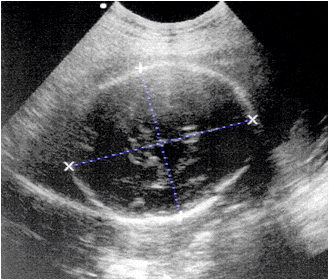

Ecografía de la región cefálica de un feto de 22 semanas que muestra el perímetro craneal de forma oval. Las marcas indican los díametros biparietal (diámetro menor) y fronto-occipital (diámetro mayor).